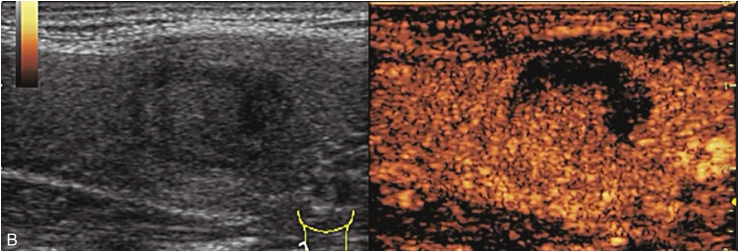

甲状腺形态基本正常,甲状腺实质回声稍增粗,分布尚均匀,甲状腺包膜尚光滑。甲状腺两叶内见多发结节,较大者位于左叶上极,呈类椭圆形,边界清楚,形态规则,纵横比<1,内部回声均匀,未见钙化,后方回声稍增强。CDFI显示左叶较大结节边缘可见丰富的条状血流信号,内部可见条状、点状血流信号,见图1-3-7。

图1-3-7 结节性甲状腺肿常规超声表现

A.常规超声图像;B.CDFI超声图像

甲状腺左叶上极较大结节增强早期呈稍高增强,自结节外周向中央灌注,增强晚期呈等增强,结节内部可见不均匀低增强区,见图1-3-8、ER1-3-4。

图1-3-8 结节性甲状腺肿超声造影图像

ER1-3-4 结节性甲状腺肿的超声造影

结节性甲状腺肿超声造影表现为病变多与周围正常甲状腺组织呈同步等或高增强,增强多较均匀,伴有囊性变者,内部可见无增强区,增强后结节边界清,周边可见环状增强,增强晚期呈等或稍高增强,也可呈稍低增强。

多早于周围正常甲状腺组织增强,从周边向中心快速充盈,呈均匀性高增强,增强后结节边界清,形态较规则,周边亦可见环状增强。

造影后结节大多呈同进或慢进,以不均匀性低增强多见,也可呈等或高增强,增强后结节边界不清,形态不规则,增强晚期可呈低增强或等增强。

图1-3-10 结节性甲状腺肿超声造影图

A.增强早期结节呈同步不均匀性等增强;B.增强晚期呈不均匀性低增强